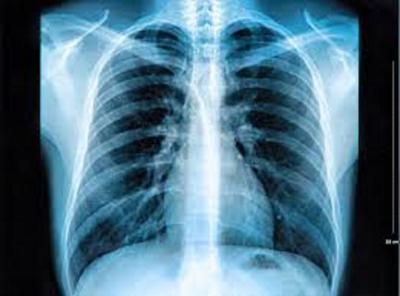

छात्रों द्वारा बनाए गए सॉफ़्टवेयर के माध्यम से एक कोरोना है या नहीं, यह केवल कुछ मिनटों में समझा जाएगा। इस सॉफ्टवेयर की मदद से मरीज का छाती का एक्सरे लिया जाता है। सीटी स्कैन किया जाता है।

एक्स-रे और सीटी स्कैन रिपोर्ट दोनों बताते हैं कि कुछ ही सेकंड में किसी व्यक्ति का कोरोना सकारात्मक या नकारात्मक है। सॉफ्टवेयर सिर्फ कोरोना नहीं बल्कि टीबी, वायरल और बैक्टीरियल निमोनिया के साथ आम मरीजों की एक्स-रे प्लेटों की जानकारी देता है।

एम्स में अगले 2 से 3 दिनों में कोरोना मरीजों की एक्स-रे और सीटी स्कैन छवियों की जांच कोरोना के सॉफ्टवेयर द्वारा की जा रही है। इसके बाद, सलाहकार समिति रोगियों की नकारात्मक या सकारात्मक रिपोर्ट का अध्ययन करेगी।